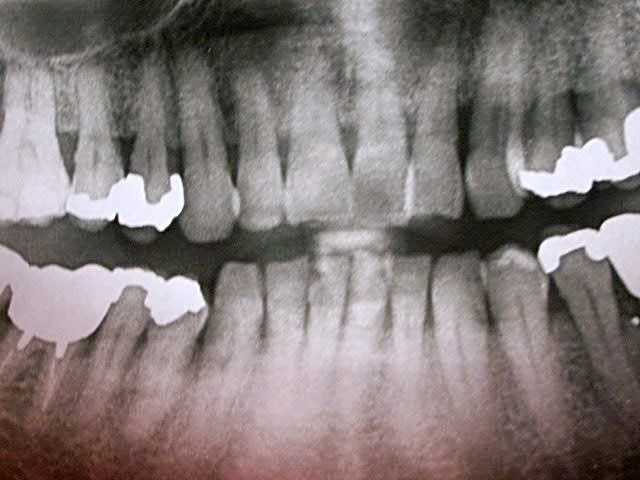

Manifestement alvéolyse horizontale généralisée, 25% de perte d'attache à 65 ans : je penche pour une parodontite chronique de l'adulte.

Suffisant s'il n'y avaient pas ces facteurs aggravants que sont les pulpectomies déficientes, couronnes débordantes et mal ajustées.

Je soupçonne aussi un trauma occlusal.

Je ne doute pas que tes talents en endo permettront de sauver ce qui l'est (bonne chance pour 36).

Mais 47 est HS.

Ouais, l'usure occlusale est quand même flagrante.

personnellement je tenterais une hemi section de la 47,gardant la racine mésiale,l'extraction de la racine distale devrait diminuer les problèmes paro de la 48, qui,si pas trop mobile,garderais

en attendant l'evolution,puis devitalisée et bridge provisoire 46 racine 47 reconstituée,et 48

moi, c'est la 17 qui me chagrine le plus.

la racine distale de 47 est morte. Première impression: la virer, garder la racine M, petit bridge pro en résine renforcée en attente de stabilisation du pb paro et assurer calage de 48. Voir par la suite pour implant ou bridge.

37: même pas sûr qu'elle soit nécrosée. Si oui, endo assez rapidement (avant soins paro).

36, lésion interradiculaire + distale: hummm...

Déjà on commencera par la base: Bilan général + dentaire + retroalvéolaires au moins sur toutes les postérieures + OHM + modéles d'étude pour analyse occlusale.

Probléme + paro que endo. Par certain sur ce coup que l'endo apporte un gros plus même si les RTE ne feront pas de mal.

Cas typique (enfin je crois) où il est urgent de ne pas extraire, ni de se jeter sur le bistouri si on se met dans un "esprit paro" et que la compliance du patient est ok, sauf 18 (dent courte + carie M) et 17??? mais risque de déporter toutes les forces de mastication à G et c'est la 37 qui va devenir douloureuse.

pour moi 17 18 28 perdues

48 pas très interessante si 18 pas conservée en plus elle est extrusée.....faire de l'odf alourdira je pense beaucoup pour un résultat pas forcemment supérieur tout en tenant compte de l'age

Mon plus gros doute concerne la 17: si je la vire, je vais entraîner une cascade d'extractions et répercuter toutes les forces de mastication à gauche. Mais bon... elle est douloureuse (impossibilité de mastiquer + mobilité) et l'alvéolyse semble totale. Je ne crois pas que l'on pourra la récupérer. Et en laissant un tel foyer infectieux, je risque d'entraîner la perte de la 16 aussi.

Je pense garder la racine M de 47 car encore bien accrochée et je ne sais pas s'il voudra faire des implants.

Bien que souhaitant pratiquer plus une paroméd, je me demande si une chir paro sur la 36 ne serait pas nécessaire. un avis?